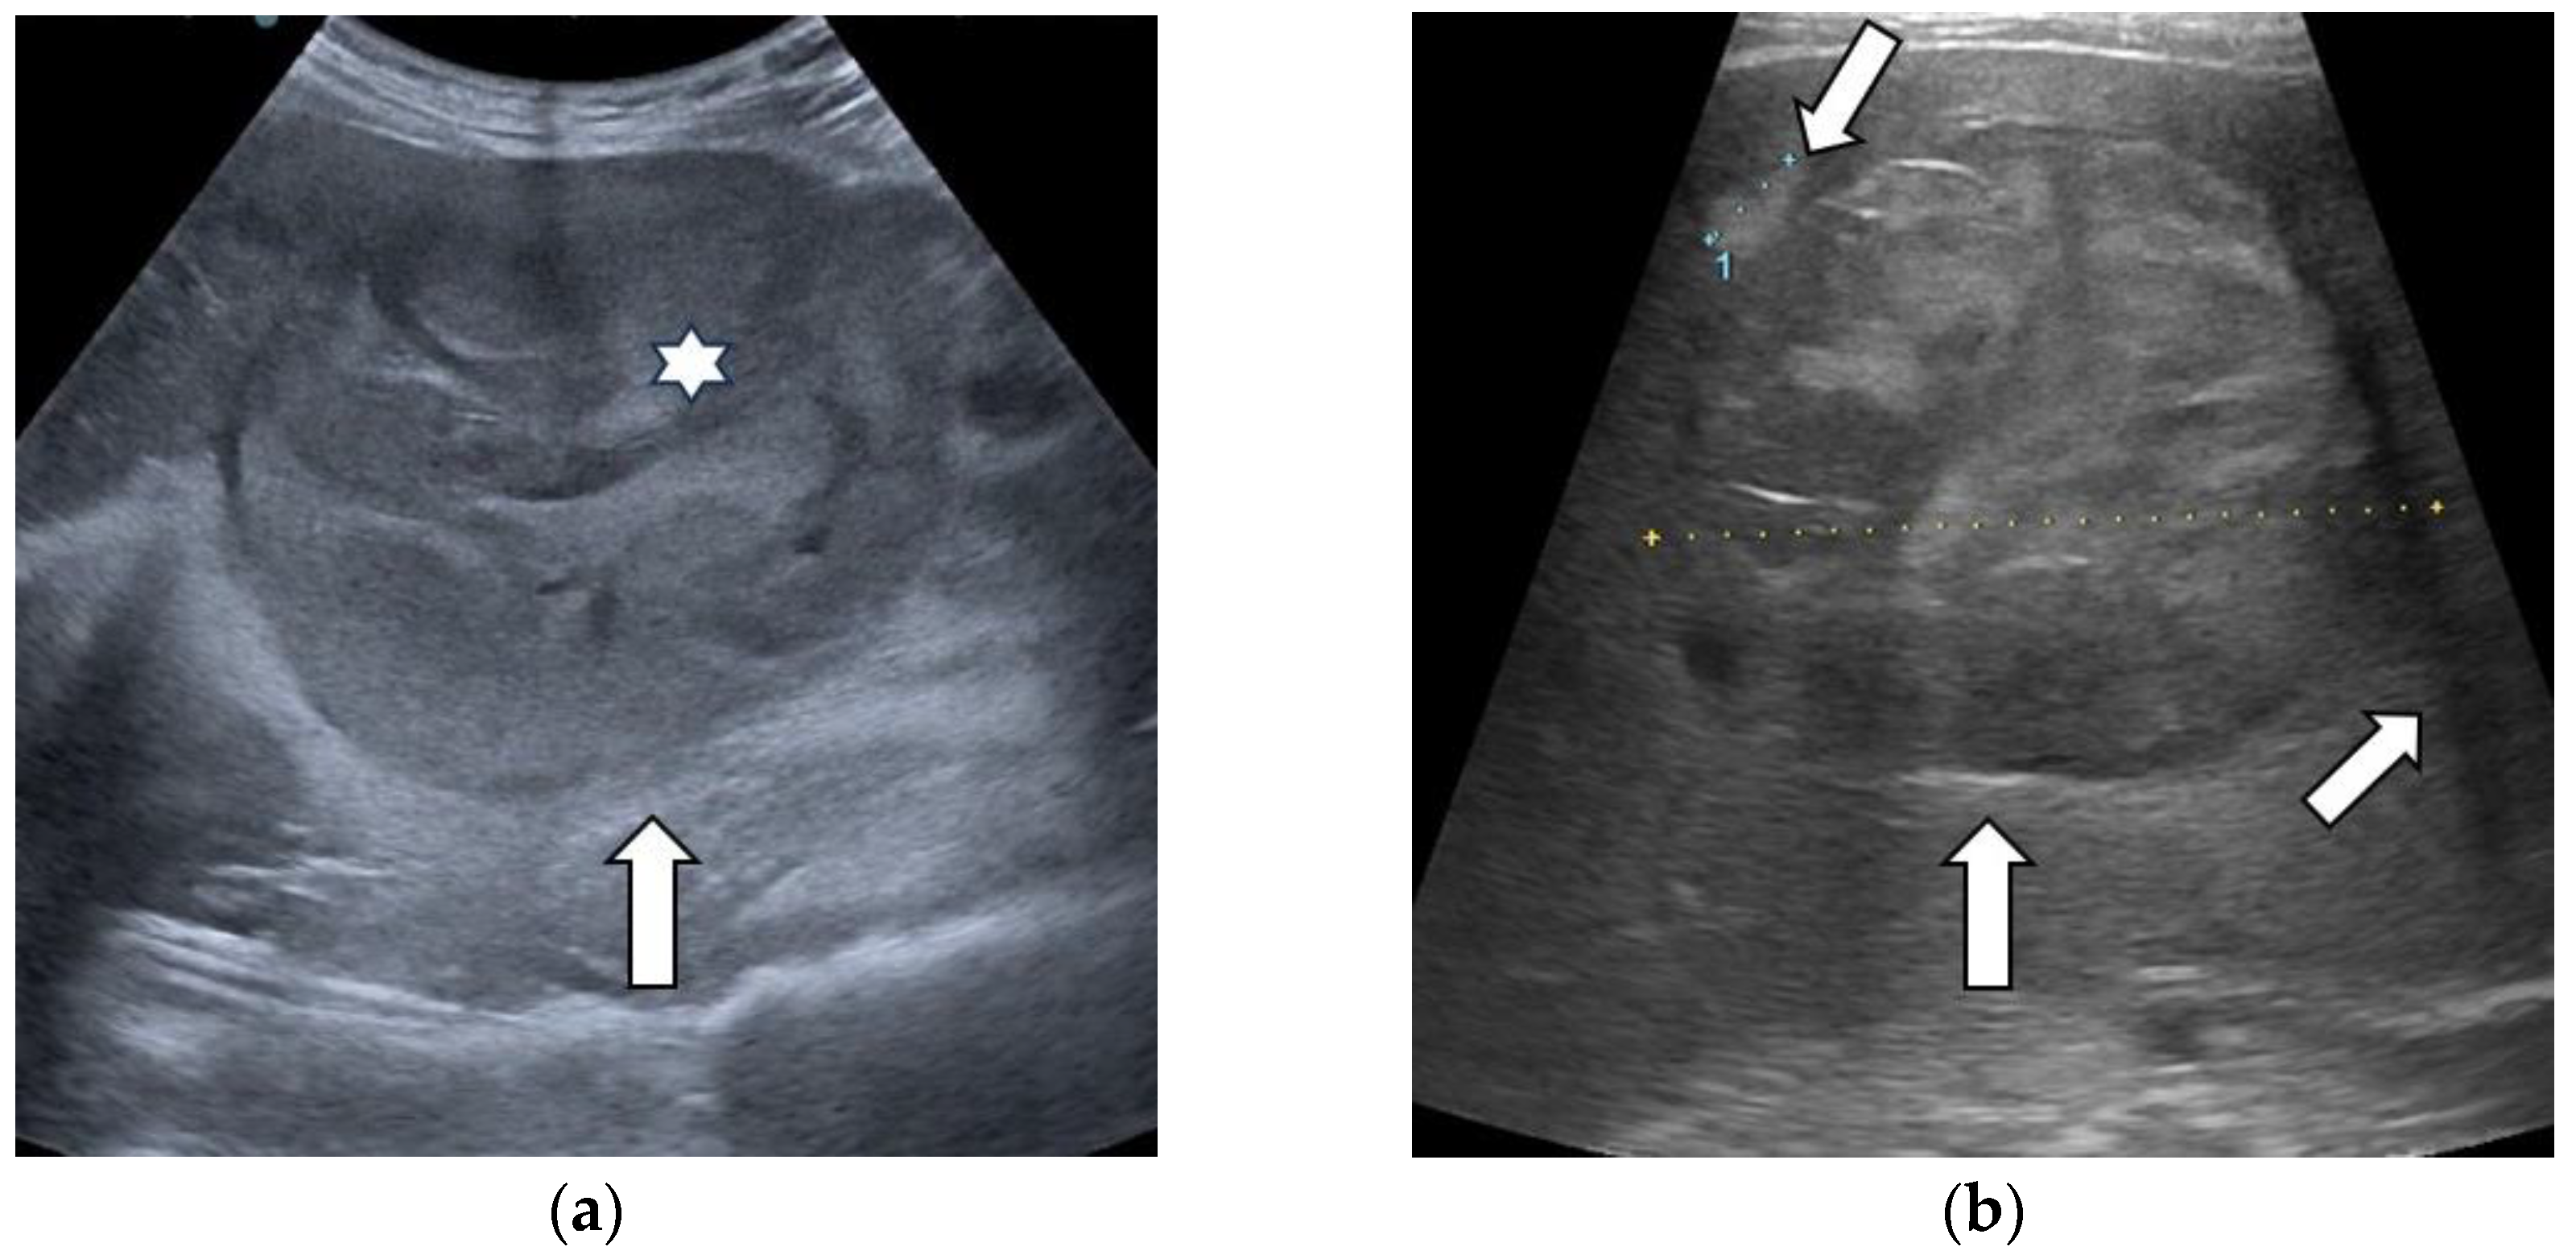

3.1. B-Mode Ultrasound

| Ultrasound Features | Entire Group | HCCs | Non-HCC Malignancies | Benign Tumors | |

|---|---|---|---|---|---|

| Size (mm) | 70.11 ± 38.97 | 76.73 ± 40.8 | 60.88 ± 30.86 | 57.93 ± 35.49 | |

| Echogenicity | Hypoechoic | 22 (30.6%) | 12 (16.67%) | 7 (9.72%) | 3 (4.17%) |

| Isoechoic | 14 (19.4%) | 9 (12.50%) | 2 (2.78%) | 3 (4.17%) | |

| Hyperechoic | 31 (43.1%) | 21 (29.17%) | 5 (6.94%) | 5 (6.94%) | |

| Mixed echogenicity | 5 (6.9%) | 2 (2.78%) | 3 (4.17%) | 0 | |

| Homogeneity | Homogenous | 5 (6.9%) | 2 (2.78%) | 1 (1.39%) | 2 (2.78%) |

| Non-homogenous | 67 (93.1%) | 42 (58.33%) | 16 (22.22%) | 9 (12.50%) | |

| Tumor boundaries | Well-delimited | 58 (80.6%) | 38 (52.78%) | 12 (16.67%) | 8 (11.11%) |

| Ill-delimited | 14 (19.4%) | 6 (8.33%) | 5 (6.94%) | 3 (4.17%) | |

| "Nodule-in-nodule” architecture | Yes | 18 (25%) | 17 (23.61%) | 1 (1.39%) | 0 |

| No | 54 (75%) | 27 (37.50%) | 16 (22.22%) | 11 (15.28%) | |

| Mosaic appearance | Yes | 16 (22.2%) | 16 (22.2%) | 0 | 0 |

| No | 56 (77.8%) | 28 (38.89%) | 17 (23.61%) | 11 (15.28%) | |

| Halo sign | Yes | 28 (38.9%) | 21 (29.17%) | 5 (6.94%) | 2 (2.78%) |

| No | 44 (61.1%) | 23 (31.94%) | 12 (16.67%) | 9 (12.50%) | |

| Satellite nodules | Yes | 8 (11.1%) | 7 (9.72%) | 1 (1.39%) | 0 |

| No | 64 (88.9%) | 37 (51.39%) | 16 (22.22%) | 11 (15.28%) | |